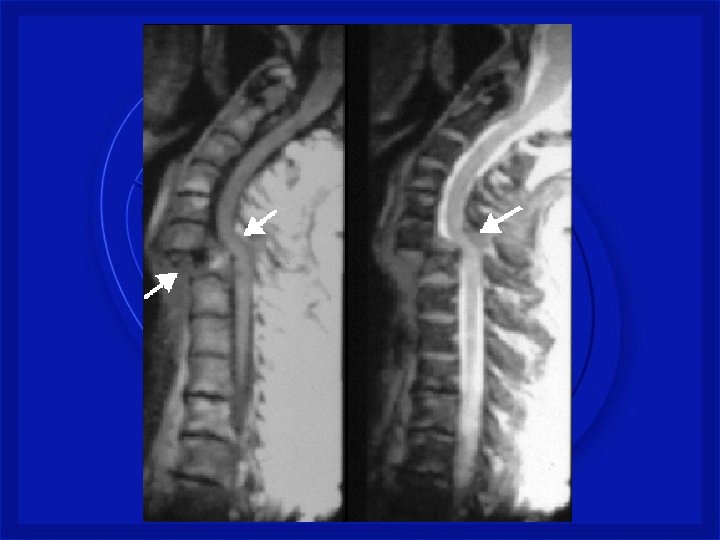

FRATURA COMPRESSÃO TORÁCICA BAIXA

FRATURA COM LUXAÇÃO COMPLETA – TORÁCICA BAIXA

LESÕES - COLUNA